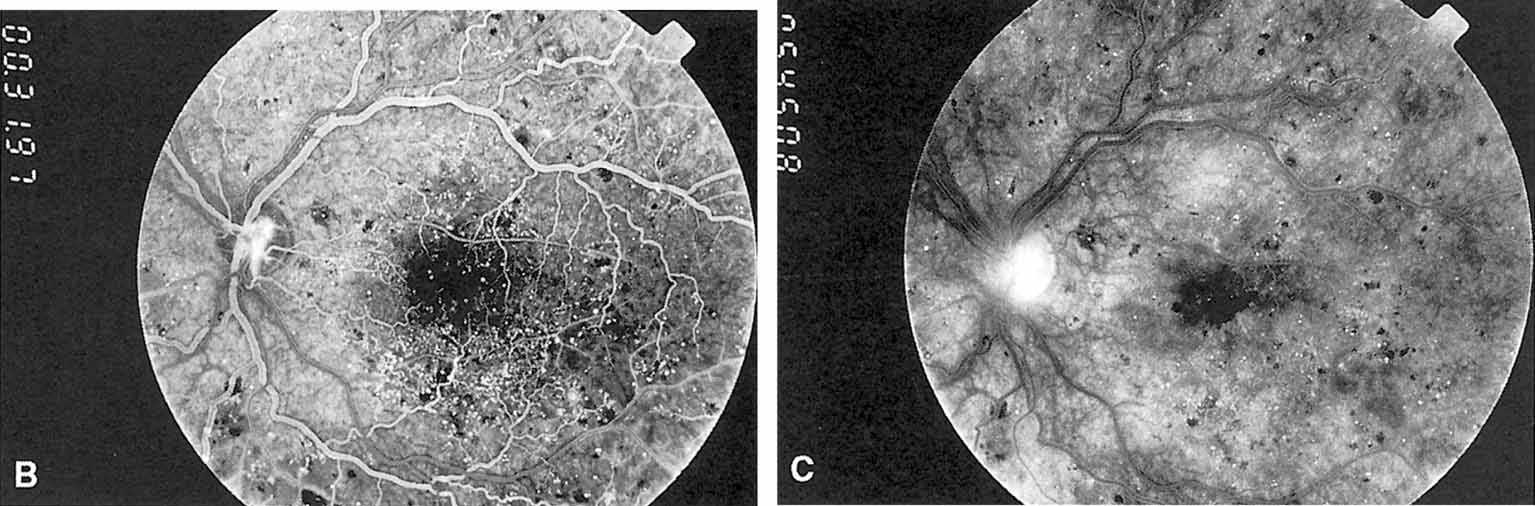

In advanced NPDR, signs of increasing retinal hypoxia appear, including multiple retinal hemorrhages, cotton-wool spots (Fig. 7), venous beading and loops (Figs. 7 and 8), intraretinal microvascular abnormalities (IRMA) (see Figs. 7 and 8), and large areas of capillary nonperfusion.

Fig. 7 A. Severe nonproliferative retinopathy with venous dilatation and beading, soft exudates, and intraretinal microvascular abnormalities B. The midphase of the angiogram shows the intraretinal microvascular abnormalities (IRMA) and severe capillary nonperfusion.

Venous beading (see Fig. 7) and venous loops (see Fig. 8) indicates sluggish retinal circulation and are nearly always adjacent to extensive areas of capillary nonperfusion. Focal vitreous traction is thought to contribute to their formation.9 Capillaries next to areas of nonperfusion that dilate and function as collaterals are referred to as IRMA. They are frequently difficult to differentiate from surface retinal neovascularization. Fluorescein, however, does not leak from IRMA but leaks profusely from neovascularization (see Fig. 7).